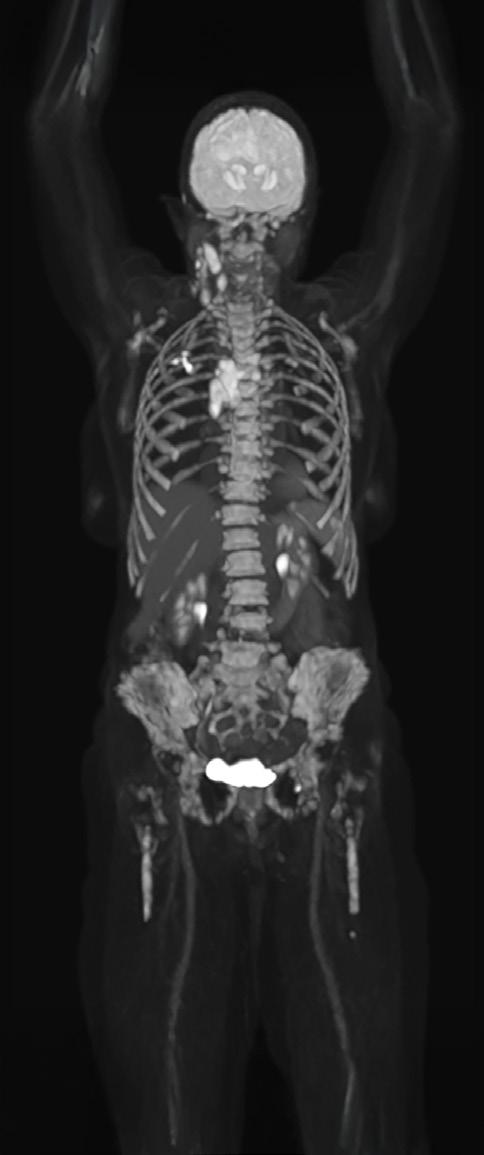

The Whole Picture: Total-Body PET and the Future of Biopharma

What if a clinical scan could transform biopharmaceutical innovation and patient care, streamlining drug development, clinical trials, and complex disease diagnosis? Total-body Positron Emission Tomography (PET) imaging is turning that vision into reality, offering a full-body, real-time view of human physiology.

Total-body PET is redefining what is possible in molecular imaging and biopharmaceutical development. This advanced PET technology can deliver full-body scans in minutes, with a sensitivity of up to 40x greater than conventional standard field PET scanners1 and potential for significantly lower radiation exposure. This opens exciting new avenues for research and discovery. It enables clinicians to study disease in real time across the whole body, revolutionising how we diagnose, stage and treat complex conditions like cancer, cardiovascular disease and neurodegenerative disorders. For patients, this means faster scans and earlier interventions, with the opportunity for more personalised treatments. For research and industry, it unlocks a powerful new platform for evaluating novel therapies, tracking their behaviour and accelerating their path to market.

But realising the full potential of total-body PET requires more than cutting-edge scanners. It demands a robust infrastructure, one that includes a reliable supply of radiotracers and an integrated framework for data sharing and collaboration. In the UK, the National PET Imaging Platform (NPIP) is building exactly that. What it reveals is not just a clearer image of the body, but a blueprint for the future of biopharmaceutical development.

Continued technological advances in hardware and software have led to a new generation of PET scanners with far greater sensitivity and resolution. While conventional PET relies on multiple bed positions and generating multiple images to acquire

a whole picture of the body, total-body PET has a field of view wide enough to take an image from head to toe in a single scan, and a detector capable of 40x higher sensitivity.¹ This means the whole body can be imaged faster, at higher resolution and in real-time. It also means lower doses of radiotracer are required to generate the same amount of detail (Table 1).1,3

Feature

Conventional PET Total-Body PET

Large Axial Field of View (LAFOV) 15–20cm >100cm*

Sensitivity Moderate Ultra-high (up to 40x higher for whole-body images)

Average Total-Body scan time** 10–30 min 30 seconds–3 minutes

Average radiation dose for a full-body scan** ~370 MBq ~9.25 MBq

Dynamic imaging potential (continuous capture of data over time)

Patient throughput

Tracers can be followed for ~3 half-lives, limiting dynamic imaging

Lower

Tracers can be followed for 5–6 additional half-lives, enabling whole-body, real-time imaging

Potential for twice as many clinical scans per day

*Scanners in the NPIP network have a LAFOV of between 106–194cm. **Based on (18F)-FDG scan procedures.

Table 1. Differences between conventional PET scanners and total-body PET scanners.1,4,5,6

Importantly, total-body PET does not replace conventional PET imaging. Conventional PET remains indispensable in clinical practice, especially when imaging needs are localised to a specific area of the body. But for complex diseases that span multiple organ systems or in cases where lower doses of radiation are required, total-body PET offers a transformative new lens: